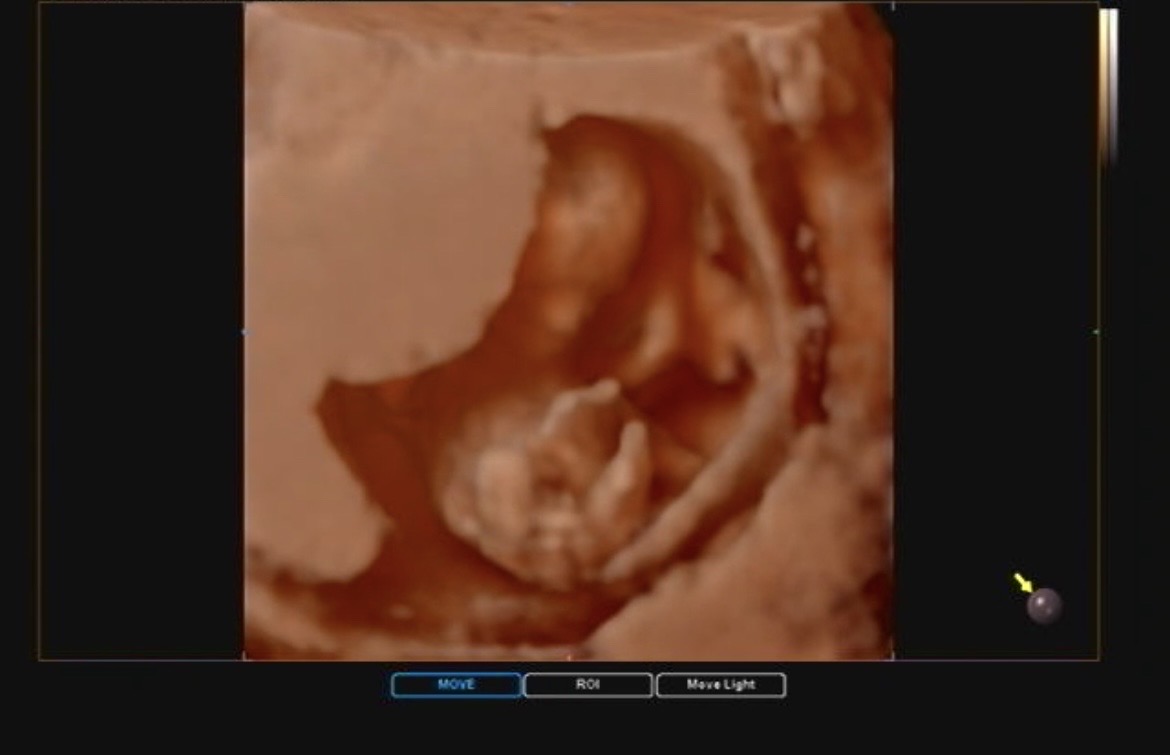

12주6일 입체초음파

성별궁금합니다 투표좀해주세용